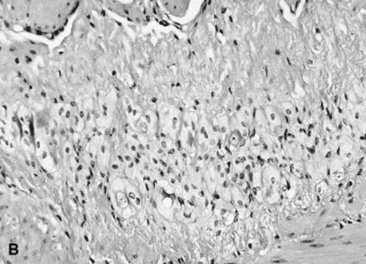

Computed tomography (CT) and magnetic resonance imaging (MRI) are of little use for evaluation of the alimentary tract (except for the head). This is mainly because of the size of the patient compared with the size of the gantry and bore in CT and MR units, respectively. Dental disorders such as abscesses and fractures can be clearly seen on CT images, especially after three-dimensional reconstructions (Fig. 32-10), and CT is also useful to detect pharyngeal and esophageal masses that may not be fully identified with conventional radiographs. CT and MRI can be used in foals that are able to be placed within the gantry or bore of the magnet; however, because of the motion of the gastrointestinal tract and the long acquisition times used with respiratory gating sequences, MRI has not been used widely to evaluate the thorax or abdomen. A single case report has been published that described the use of contrast esophagraphy and CT to aid in the surgical planning of a persistent right fourth and left sixth aortic arch that caused a vascular ring anomaly in a foal.17 However, the applications for these technologies have yet to be realized.

Fig. 32-10 These are transverse (A) and three-dimensional reconstructed computed tomography images (B) of the head of a 4-year-old pony mare with chronic draining tracts from the mandible. The arrows illustrate the tract through the mandible that communicates with the apical portion of the left mandibular first molar (tooth #309).